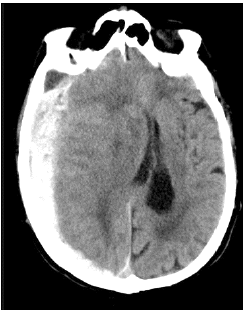

Paciente, sexo feminino, 82 anos, sofreu queda da própria altura após tropeçar no tapete da sala de sua casa. Após a queda, familiares notaram que a paciente apresentava lentificação psicomotora, sonolência excessiva e confusão mental, sendo, então, levada ao hospital local para atendimento médico. Na admissão hospitalar realizou tomografia computadorizada de crânio que evidenciou o seguinte resultado:

Qual o achado da tomografia de crânio realizada?